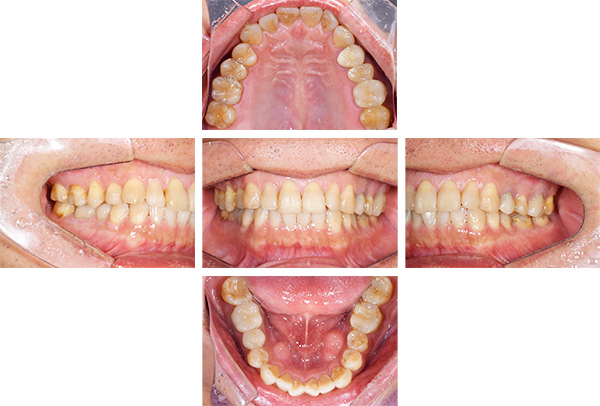

インレー症例

治療前

治療後

治療期間 8回(2ヶ月)

費用 ・セラミックインレー9本

合計:495,000円

治療リスク・副作用 ・詰め物、被せ物をする時は自分の歯を削ることになります

・歯ぎしり・食いしばりが強い方は、セラミックが割れてしまうことがあります。

治療期間 4回(1ヶ月)

費用 ・セラミックインレー10本

合計:550,000円